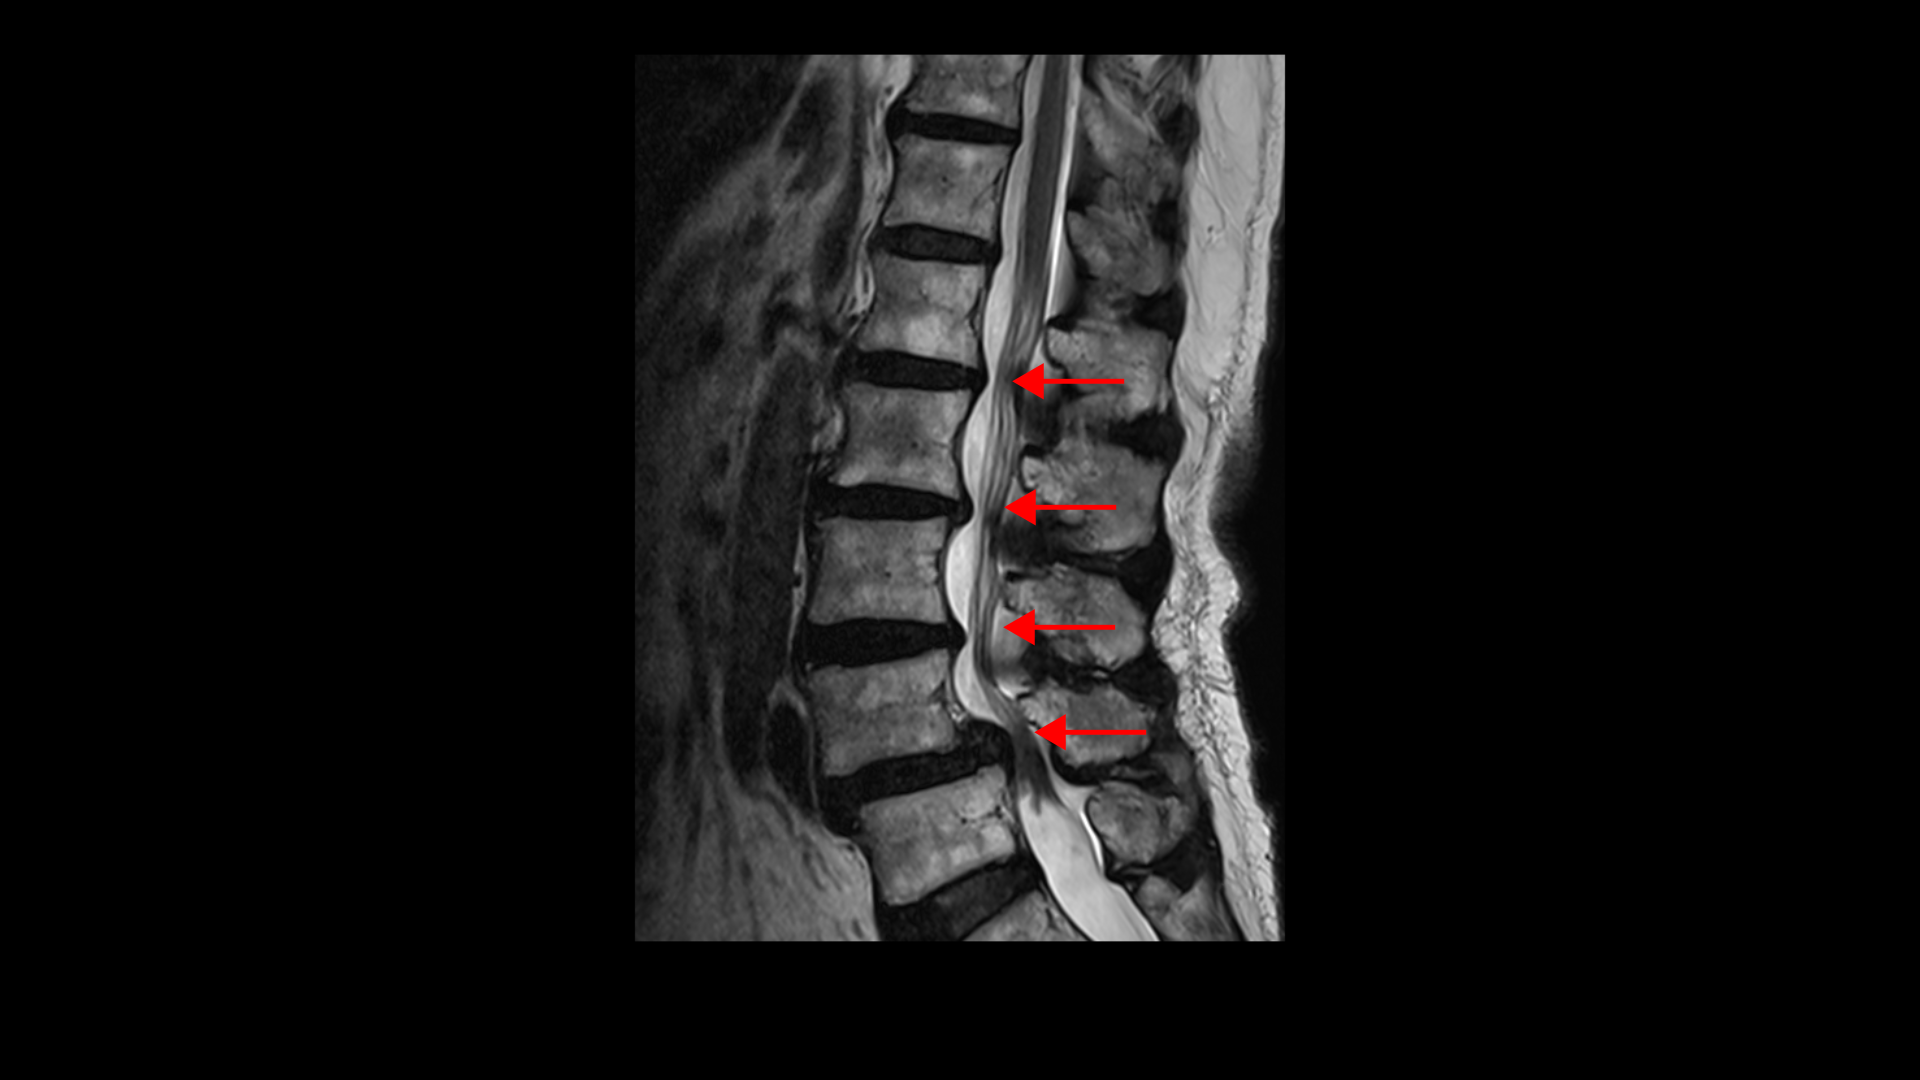

이 환자분 상태를 먼저 설명 드린 후 이분 말씀을 들어보겠습니다. 이분은 협착증을 앓으신 지 약 7년 정도 되셨습니다. MRI를 보면 여러 마디에 퇴행성 디스크가 있고

4번, 5번에는 전방전위증이 있습니다.

전방전위증이 있는 4번, 5번 마디에서는 오른쪽, 왼쪽 신경가지가 나가는 양쪽 추간공이 모두 좁아져 있고

그리고 척추관도 황색인대가 심하게 두꺼워지면서 중심성 협착도 매우 심합니다.

4~5년 전부터 허리와 다리 통증이 심해졌고 걸을 수 있는 거리가 점점 짧아져 올해부터는 100m 정도만 걸으면 쉬어야 되는 상태까지 악화됩니다. 이처럼 협착증은 해가 갈수록 증상이 악화되어 결국은 걸을 수 있는 거리가 점점 짧아져 종국에는 몇 걸음 밖에 못 걷게 되는 것이 특징인데요. 그런데 이렇게 해가 갈수록 협착증 환자의 증상이 나빠지는 걸 MRI에서 신경구멍만 보고 신경이 많이 눌리니까 그런다고만 설명하는 경우가 많습니다. 그러니까 수술해서 신경구멍을 넓혀야 한다는 거죠. 그래서 이 환자분도 신경구멍을 넓히는데 뼈가 밀려 나가 있으니까 나사 박는 유합술을 해야 된다고 대학병원에서 들으셨습니다.